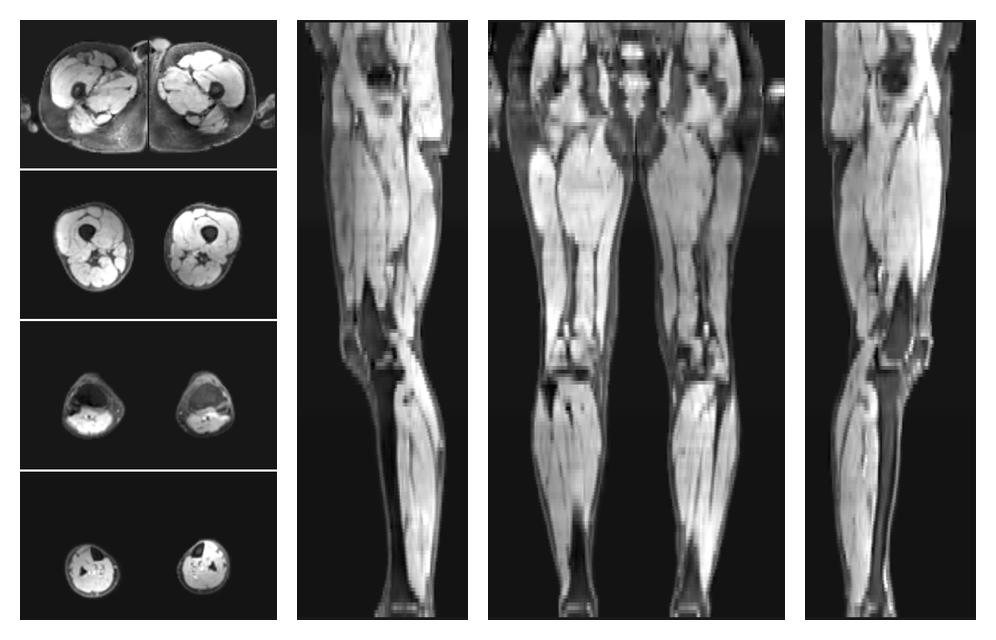

• Water only signal

The water part of the acquired multi-echo spin echo data.